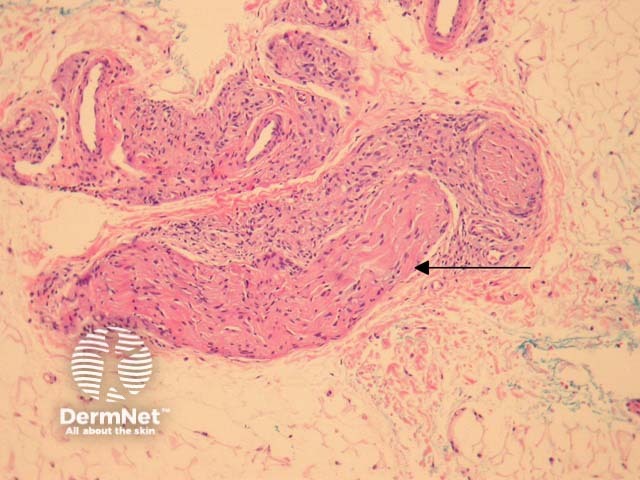

Tuberculoid leprosy – There is a tuberculoid or sarcoidal granulomatous reaction throughout the dermis consisting of some Langhans giant cells, macrophages in tight clusters, and few accompanying lymphocytes (figure 3). The infiltrate may extensively infiltrate peripheral nerves (figure 4, arrow), vessels, the overlying epidermis and arrectores pilorum.

Figure 3

Figure 4